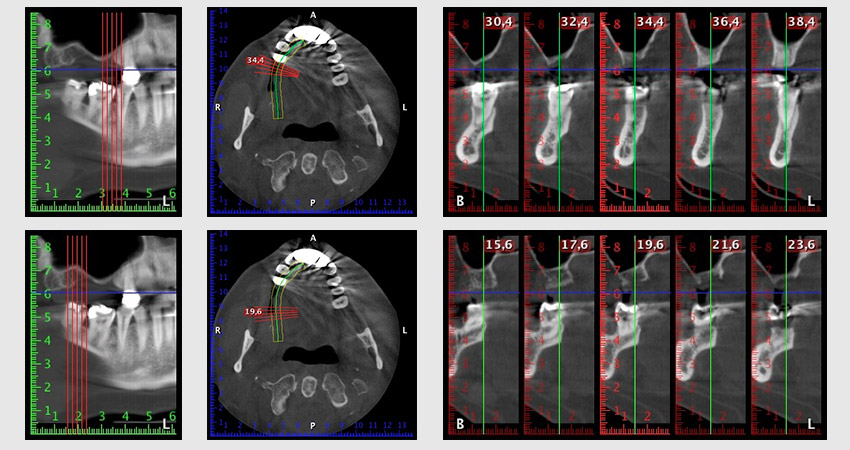

Al fine di pianificare e minimizzare i rischi, circa sei mesi dopo l'estrazione dei denti 16 e 14 viene effettuata una tomografia digitale volumetrica (DVT, Planmeca), la quale conferma chiaramente la mancata rigenerazione ossea nel volume desiderato (da fig. 2 a 7).

Implantologia

Da immagine 2 a 7: DVT con volume osseo orizzontale notevolmente ridotto.

È necessario un rialzo del pavimento sinusale nelle regioni 16 e 14 per garantire una solida ricostruzione basata su almeno due impianti. Si auspica un accrescimento osseo su scala relativamente ampia a causa del volume osseo residuo estremamente ridotto in questo caso. Le principali procedure di accrescimento osseo sono invasive e incrementano il tasso di morbilità dei pazienti, oltre a essere costose in termini di tempo e denaro. Prevedere l'esito del trattamento diventa più difficile e il rischio di insuccesso aumenta. Il dentista informa la paziente e le propone una soluzione asportabile, fermamente rifiutata.

Per ridurre l'accrescimento nella regione 14, con il consenso della paziente si opta per il posizionamento e l'inclinazione dell'impianto 16 in direzione dorso-craniale (fig. 8).

Immagine 8: DVT con piano dell'angolo di inserimento per impianto 16